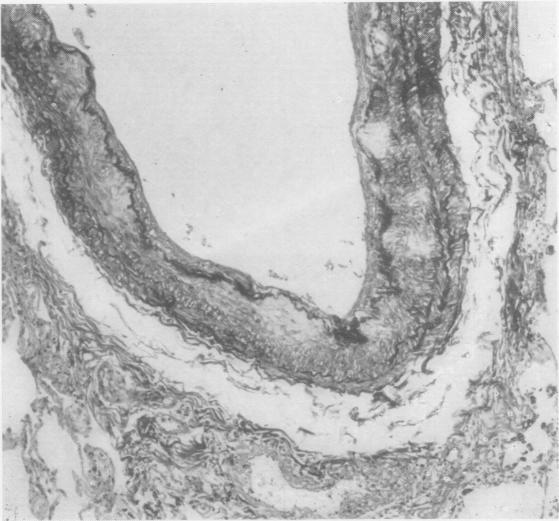

Primary amyloidosis: a review.

J Clin Pathol. 1956 Aug;9(3):187-211. doi: 10.1136/jcp.9.3.187.